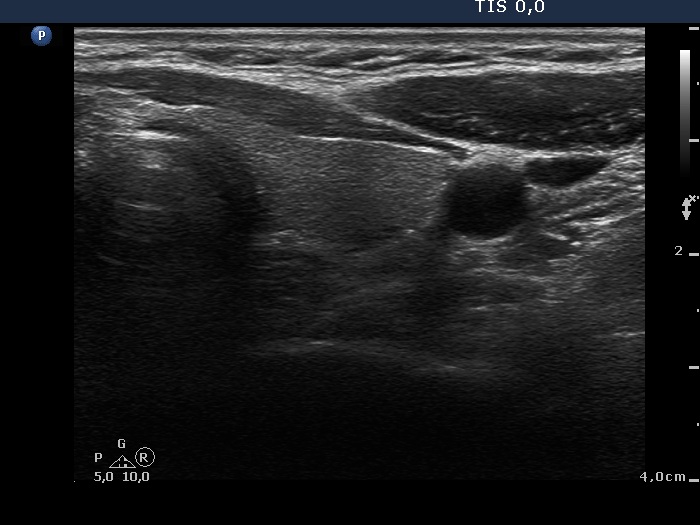

Intranodular hyperechogenic figures - case 624 (ultrasonographic picture 7)

Left lobe, transverse scan. This lobe is intact.